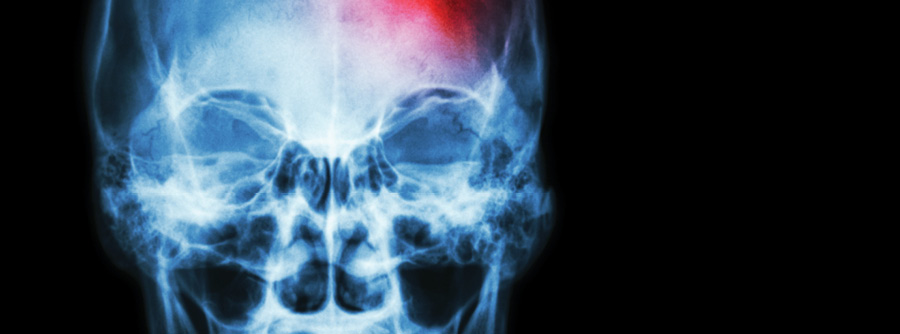

Stroke, or cerebrovascular accident (CVA), is caused by the sudden interruption of blood supply and oxygen to the brain. While 75% of those who suffer a stroke survive, 20% initially require some type of institutional care and 15% or more suffer permanent disabilities. This is because stroke almost always results in damage to brain tissue.

The most common type of stroke is ischemic stroke, which occurs when cerebral arterial blood flow is disrupted. Ischemic stroke may be caused either by a blood clot that forms in intracranial vessels (as a result of atherosclerosis) or by a clot that forms elsewhere in the body (in the heart, for example, as a result of atrial fibrillation) and then migrates to the brain. Since certain functions are linked to specific regions of the brain, the patient with ischemic stroke will display symptoms of changes in physical or mental status, based on the specific location in the brain where the ischemic damage occurred.

Stroke may also result from hemorrhage. Hemorrhagic stroke results from intracerebral and subarachnoid hemorrhage when bleeding occurs directly into brain and central nervous system tissues. Symptoms resulting from hemorrhagic stroke are more difficult to interpret and predict, since additional tissue trauma, resulting from increased intracranial pressure and edema, may exacerbate brain tissue damage caused by the initial hemorrhage.